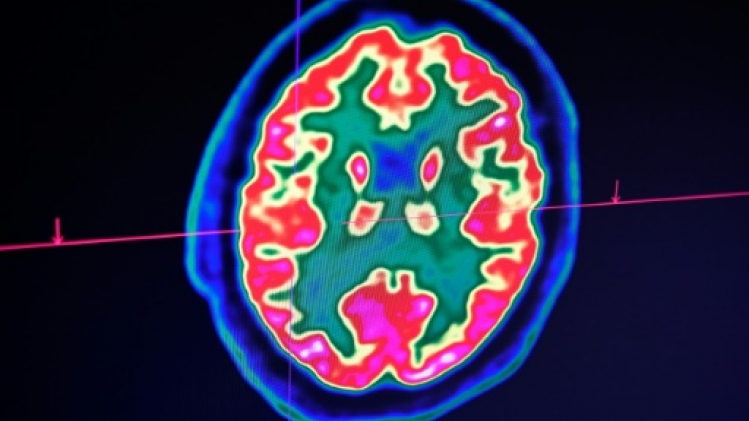

Or, depuis les années 2010, certains progestatifs se sont révélés favoriser l'apparition de méningiomes. Ces tumeurs au cerveau sont parfois qualifiées de "bénignes", car elles ne sont pas susceptibles de dégénérer en cancers mortels, mais elles peuvent provoquer de graves handicaps neurologiques.